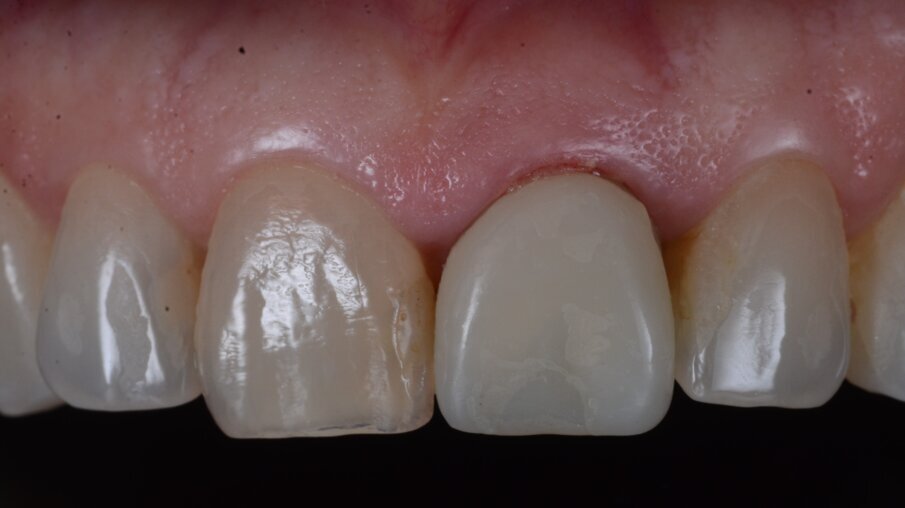

Una paziente di 53 anni si è presentata in studio con un incisivo sinistro fratturato a cui era stata più volte cementata una corona di ceramica (Figg. 1, 2). L’anamnesi e gli esami hanno evidenziato una buona salute sistemica e orale, un’occlusione ben equilibrata e nessuna abitudine al fumo. La tomografia cone beam (CBCT) e la radiografia periapicale hanno mostrato un riassorbimento radicolare esterno con inserimento nell’osso alveolare molto scarso, insufficiente per un adeguato posizionamento di un comune perno endocanalare (Figg. 3, 4). Considerando che il dente fratturato si trovava nella zona estetica, il paziente richiese un restauro nel modo più sicuro e più veloce possibile.

Fig. 1_Situazione iniziale, visione extra-orale.

Fig. 2_Situazione iniziale, visione intra-orale.